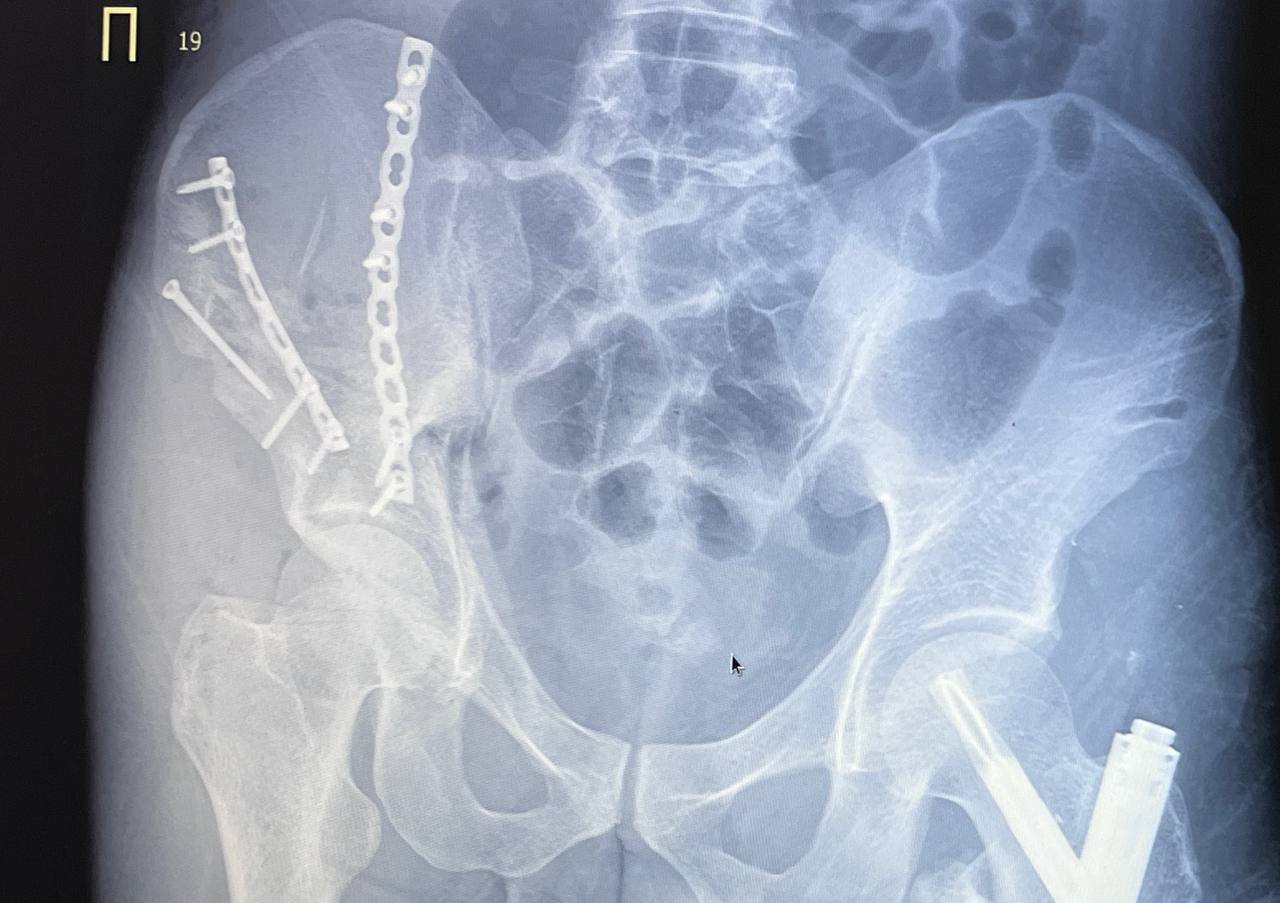

У поступившего в тяжелом состоянии 33-летнего пациента диагностировали перелом таза с центральным вывихом бедра, почти полное раздробление половины таза, перелом левого бедра. Травматологи-ортопеды провели 3 операции, в ходе которых закрепили кость левого бедра штифтом, а кости правой части таза собирали буквально по кусочкам.

«Пациенты с такими травмами поступают нечасто, и проведение масштабных операций на тазовой области в нашей практике — тоже редкое явление. На сегодняшний день состояние пациента улучшается — конечности уже освобождены от внешней фиксации, раны заживают, пациент постепенно восстанавливает активность», – рассказал заведующий травматологическим отделением №3 Евгений Молоков.